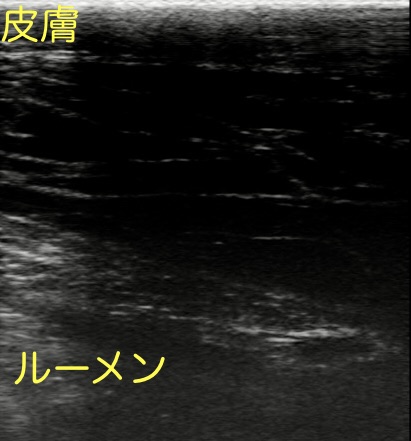

繁殖検診で用いる直腸用プローブを、左下腹部の皮膚に押し当てて見てみました。

二箇所、場所をずらして撮ったものです。

いずれも皮膚と腹腔臓器の間の筋層が網目状に広がっているように見えます。

低エコー(黒っぽく映ること)に映るのは炎症により血管から漏出した漿液または血液と推察されます。

消化管(内腔に流動性が見られる管腔状の構造)は映らず、均一な構造でもないことから、類症鑑別①②の可能性は否定されました。